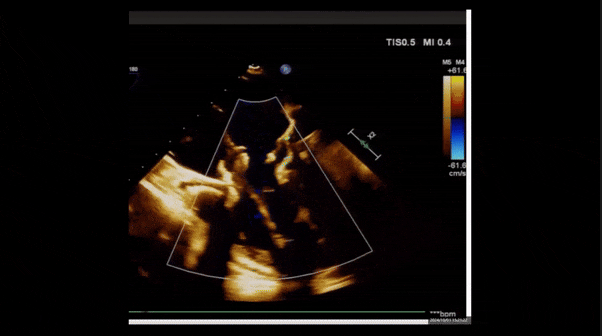

2、彩色多普勒顯示:收縮期三尖瓣口返流束起源于后隔交界、前后葉之間及前隔交界,返流束縮流頸最大寬度27mm,三尖瓣返流口EOA=2.02cm2,返流容積124ml,收縮期三尖瓣返流峰值速度2.64m/s,返流峰值壓差28mmHg,PAPs 43mmHg,舒張期三尖瓣口平均跨瓣壓差1mmHg,肝左靜脈可見明顯逆向血流波。

術(shù)后即刻返流

術(shù)前術(shù)后返流情況對比